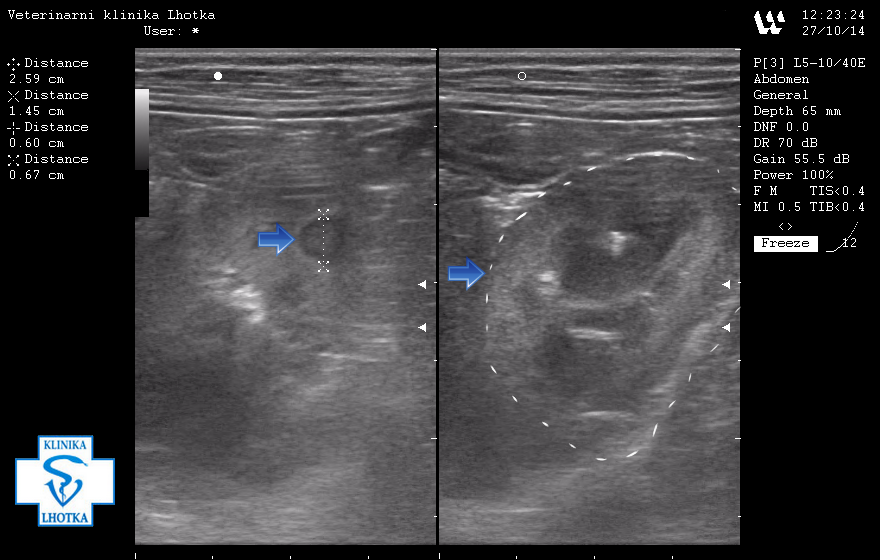

Na ultrazvukových snímcích jsou šipkami označeny metastázy v oblasti jater, levé ledviny, pravděpodobně i v močovém měchýři a v mízních uzlinách pod bederní páteří.

Zde je šipkami ohraničená oblast, kde přechází normální struktura jater v metastázi.

SONO jater - metastáza nádoru mléčné žlázy2